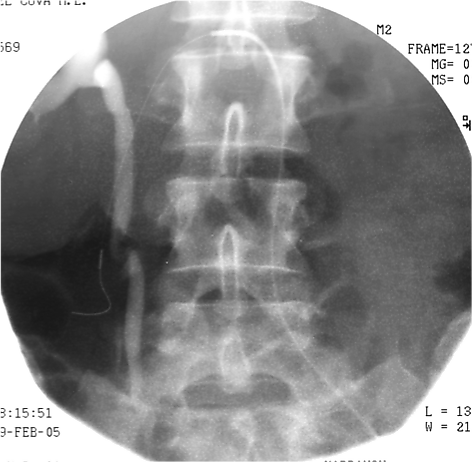

Эмболизация маточных артерий (ЭМА) — способ лечения миомы матки без хирургической операции. Эффект достигается за счет перекрытия кровотока в узлах миомы с помощью специального препарата, который вводится в артерии матки по тонкой трубке (катетеру) через бедро. Препарат содержит мелкие шарики (эмболы), которые перекрывают артерии миомы, после чего она погибает в течение нескольких часов. Эмболизация маточных артерий позволяет во многих случаях отказаться от необходимости удаления матки при миоме и сохранить репродуктивную функцию.

При миоме ЭМА вызывает прекращение кровотока по ветвям маточных артерий, кровоснабжающим миому. Разный диаметр питающих миому ветвей и ветвей, питающих миометрий, приводит к минимальному воздействию на сосуды неизмененного миометрия. После прекращения кровоснабжения мышечные клетки, формирующие миому, гибнут. В течение нескольких недель происходит их замещение соединительной тканью. Затем в процессе «рассасывания» этой ткани происходит значительное уменьшение и/или полное исчезновение узлов, а симптомы миомы проходят.